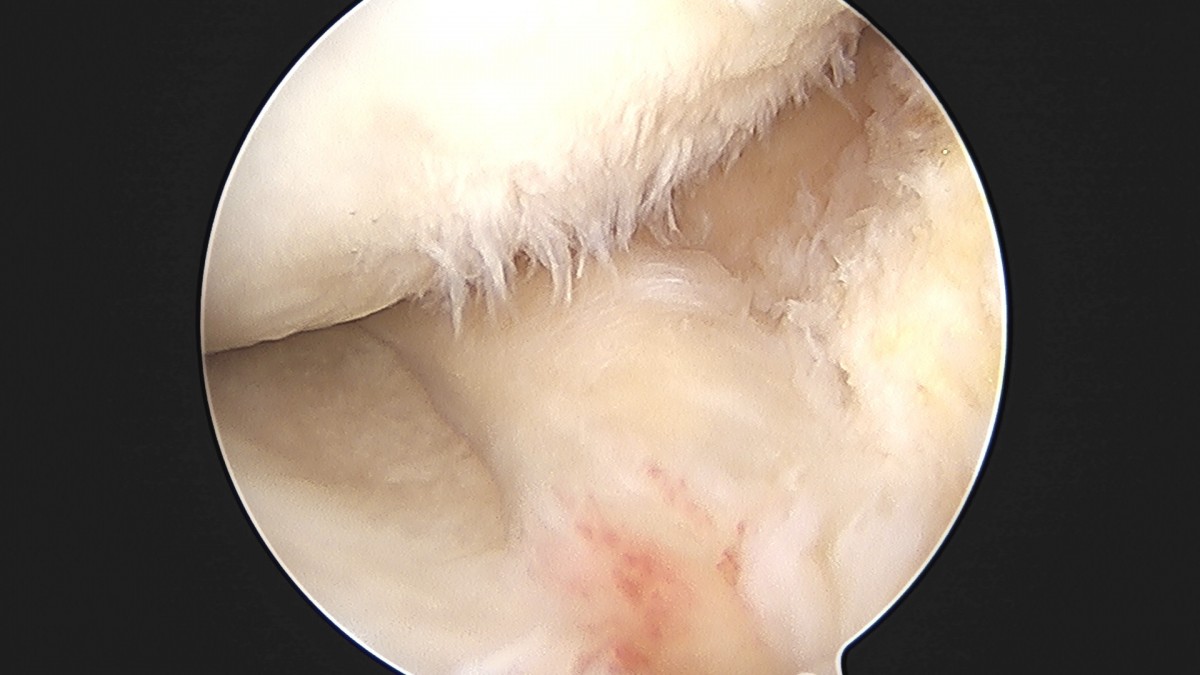

이재상원장님 무릎 반월상 연골판 절제술 박민O 환자

dae765e4d9ac96aee867c9d6292d8784_1758005185_2859.jpg